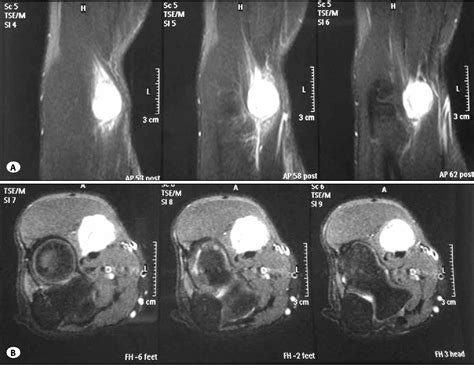

Magnetic Resonance Imaging (MRI) Provides high-resolution images of soft tissues, ideal for visualizing nerves.

• nerve sheath tumor radiology